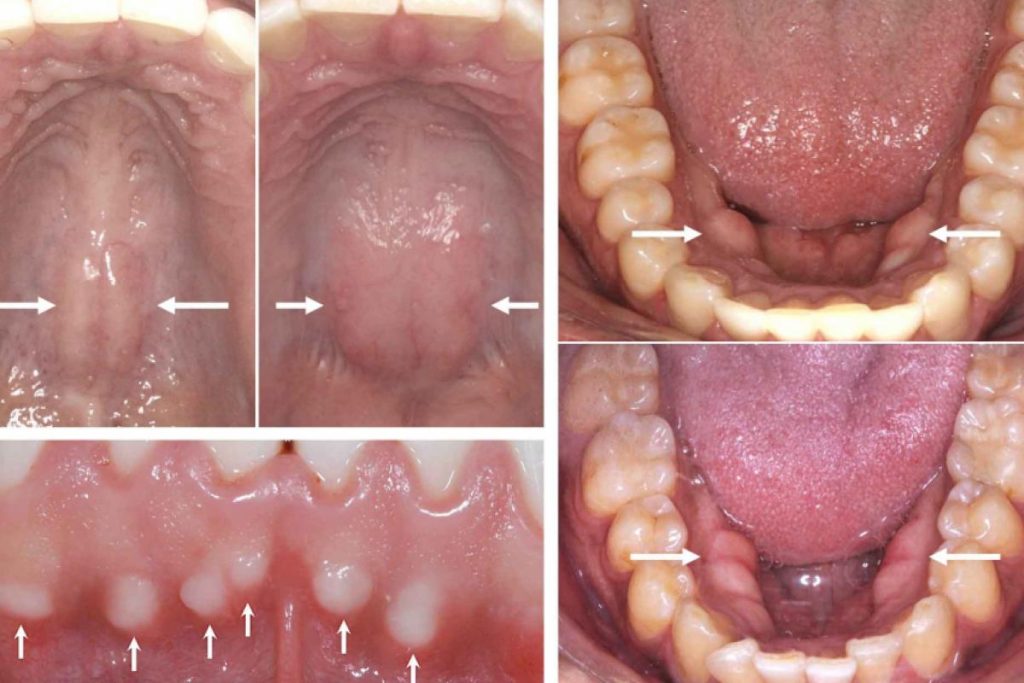

Quando se compara as partes internas da boca com as de outras, ou quando a pessoa vai ao consultório, o profissional fala que tem um Toro Palatino ou Toros Mandibulares, isto preocupa o paciente que precisa de informações seguras.

Estes crescimentos limitados para fora da superfície óssea normal ou exostoses, são também conhecidas como Toros e existem várias outras partes do corpo que tem estruturas chamadas de Toros. O Toro Palatino e os Toros Mandibulares são muito comuns, chegando a 25% em certas populações.

Na linha média do palato duro, o Toro tem superfície lisa, podendo ser lobulado. O tamanho varia desde muito pequeno até com 2 a 3cm no longo eixo e altura de até 1cm. Já nos Toros Mandibulares, em cada 10 pacientes, 2 são unilaterais, podendo também ser muito grandes em alguns poucos casos.

Eventualmente, algumas pessoas têm múltiplas exostoses na gengiva superior ou inferior, como se fossem calosidades duras, mas não recebem o nome de Toros, e sim de exostoses vestibulares da maxila ou da mandíbula. São variações da normalidade no crescimento, não precisam ser removidas, apenas se houver razões estéticas ou necessidades terapêuticas em tratamentos reabilitadores, ortopédicos ou ortodônticos.